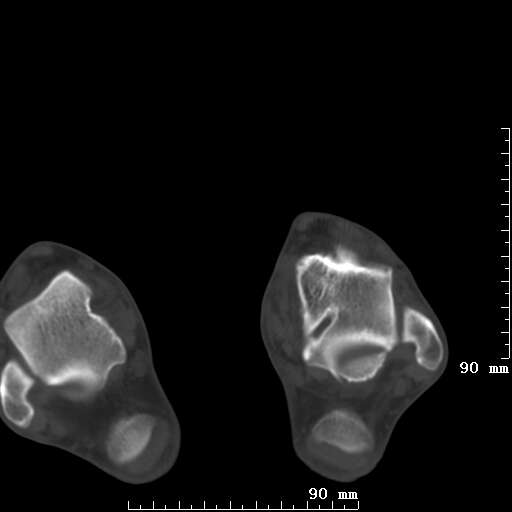

标题: CT19820:外伤一天,如何定性.男27Y [打印本页]

标题: CT19820:外伤一天,如何定性.男27Y

排除下创伤性关节炎吧,距骨有些囊变和硬化,周围韧带软组织有些机化、钙化。不是很像距骨无菌性坏死,感觉在关节面上的多,而不是距骨里面。

未见骨折及脱位像。距骨像是剥脱性软骨炎

支持!(踝关节距骨表面囊变和硬化 缺损)

距骨剥脱性软骨炎可能;踝关节创伤性关节炎?

未见明确新鲜骨折改变,距骨剥脱性软骨炎或踝关节创伤性关节炎可能。

关节周围多发高密度影,要结合病史